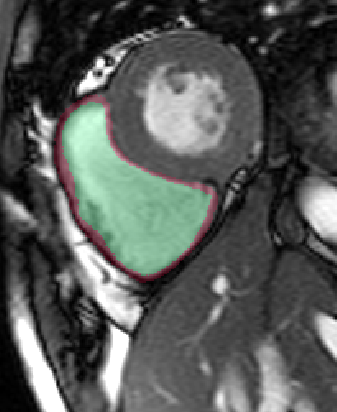

Table 2 summarizes the results of our method for RV segmentation in terms of image-based metrics. The results show that the algorithm performs better at ED than ES. This can be explained by the fact that the image quality is higher at ED than at ES. By analyzing the DM and HD on a slice-basis, it can be seen that the proposed method has a high performance on basal slices, with an average and . However, the segmentations on apical slices are of lower quality affecting the overall DM and HD scores. Figure 3 shows segmentation results in six different cases obtained from the challenge that illustrate the differences between basal and apical segmentations.

The results show that the method perform well on average but there are some cases in which it fails. In particular, our method has a very high performance on the basal slices, whereas the scores obtained for apical slices are lower (Figure 3). These can be explained by two factors: 1) The image quality at the apical slices is rather low. As the registration, the atlas ranking and the label fusion are intensity-based, poor image quality can affect the results, and 2) the regions to be segmented at the apical slices are rather small, which implies that the atlases’ masks are also small at these slices. When the masks are used in the registration process to supress undesired structures, the remaining information is insufficient, causing the intensity-based registration, rigid or non-rigid, to fail.